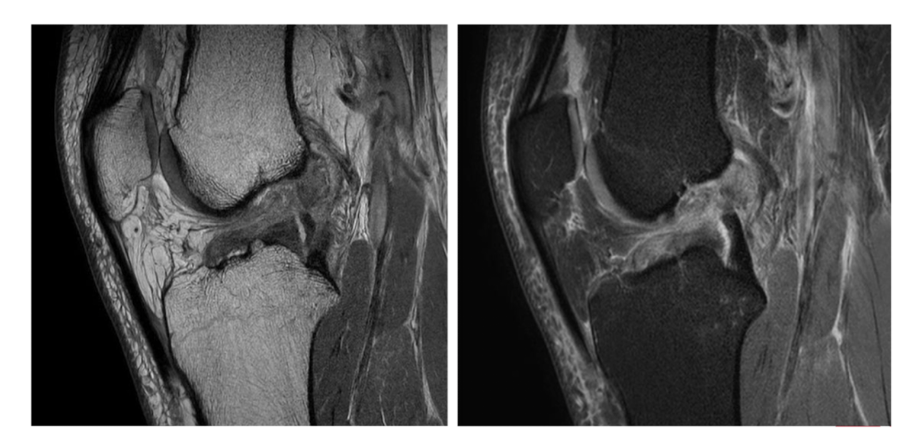

Sequence + pathology?

• 1st = PD: intermediate signal from muscle and fat is bright, image quality is much better

• 2nd = PD FS: fat has been supressed appearing much darker

• Path = complete ACL tear: in a normal knee you would see a black band which is the acl sitting

across the anterior aspect of the tibia and extending to the posterior aspect on the femur. This is not present at all hence, a tear.